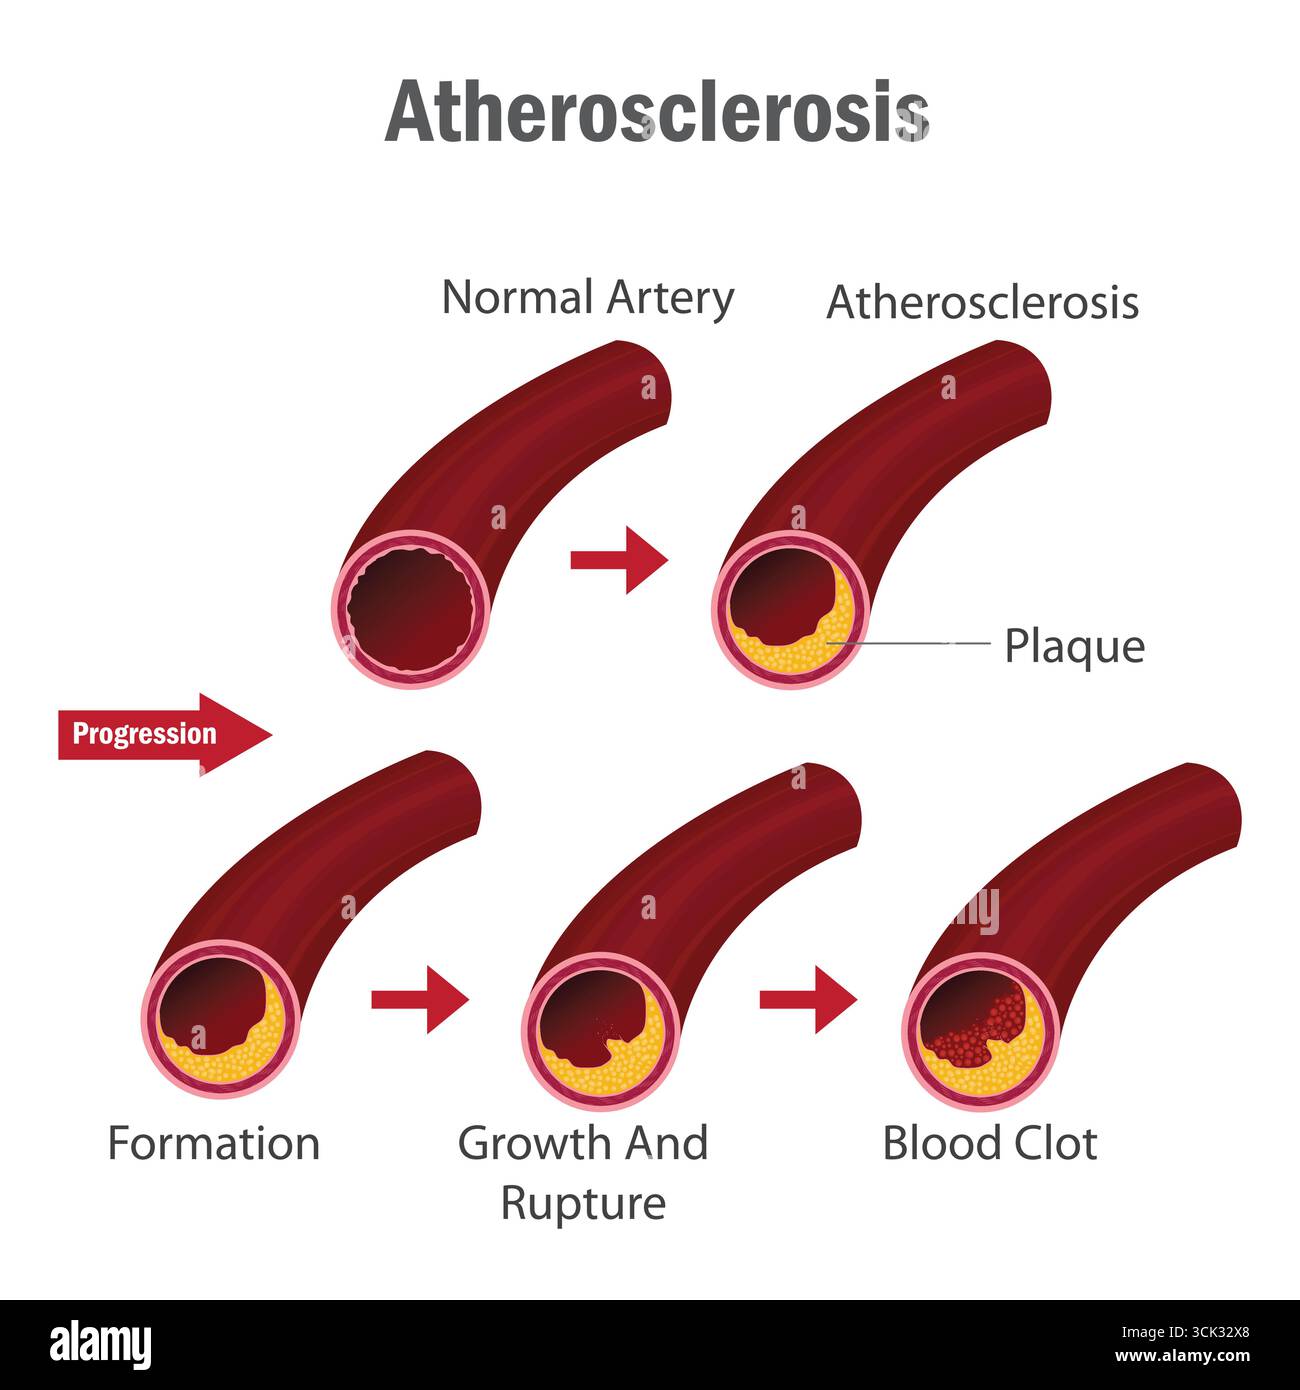

Atherosclerosis Stages Infographic Showing Artery Plaque Formation, Growth, Rupture, and Blood Clot Development in Human Circulatory System. Stock Vectorhttps://www.alamy.com/image-license-details/?v=1https://www.alamy.com/atherosclerosis-stages-infographic-showing-artery-plaque-formation-growth-rupture-and-blood-clot-development-in-human-circulatory-system-image700161344.html

Atherosclerosis Stages Infographic Showing Artery Plaque Formation, Growth, Rupture, and Blood Clot Development in Human Circulatory System. Stock Vectorhttps://www.alamy.com/image-license-details/?v=1https://www.alamy.com/atherosclerosis-stages-infographic-showing-artery-plaque-formation-growth-rupture-and-blood-clot-development-in-human-circulatory-system-image700161344.htmlRF3CK32X8–Atherosclerosis Stages Infographic Showing Artery Plaque Formation, Growth, Rupture, and Blood Clot Development in Human Circulatory System.